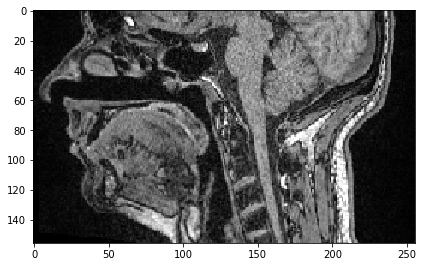

También podemos seleccionar un plano donde todos los píxeles tengan la misma posición Y. Solo necesitamos especificar que nos gustaría mantener todos los píxeles en Z usando la sintaxis :.

slice_image = image[:, 100]

imshow(slice_image)

<matplotlib.image.AxesImage at 0x2b54f836af0>

../_images/ad292cbffaab643c3d9273781ac2d7a8cb9aeed56d351d1c201b74c79fcbef31.png